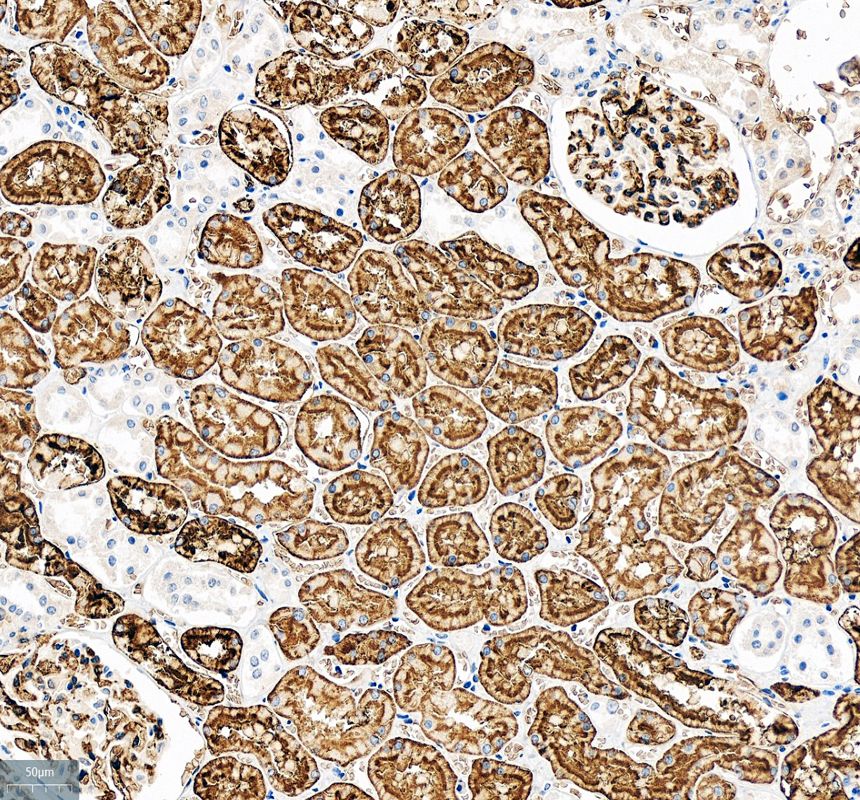

IHC analysis of AQP1 using anti-AQP1 antibody (PB9473).

AQP1 was detected in a paraffin-embedded section of human kidney tissue. The tissue section was incubated with rabbit anti-AQP1 Antibody (PB9473) at a dilution of 1:200 and developed using HRP Conjugated Rabbit IgG Super Vision Assay Kit (Catalog # SV0002) with DAB (Catalog # AR1027) as the chromogen.